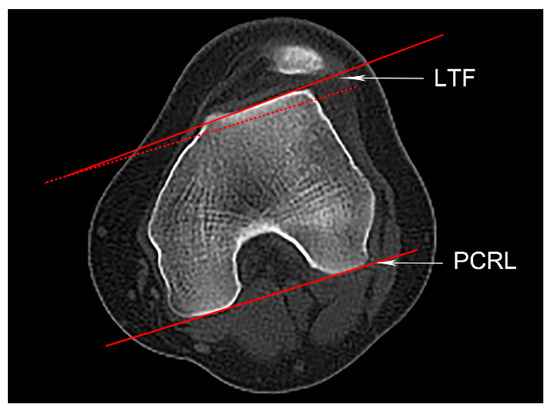

2.4.4. Knee Joint Rotation and Patellar Height